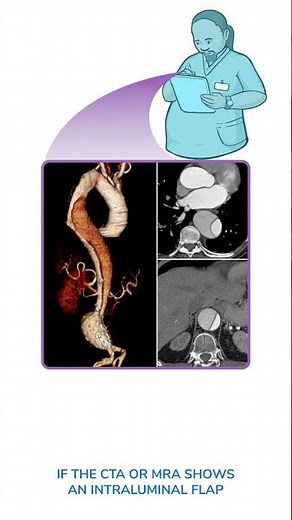

Aortic Dissection #medicine #vascularsurgery

Aortic Dissection

Aortic Dissection Explained in 3 Minutes | First Aid USMLE Step-1 High Yield

Aortic dissection Stent grafting #cardiology #shorts

Diagnostics on Demand: Aortic dissection